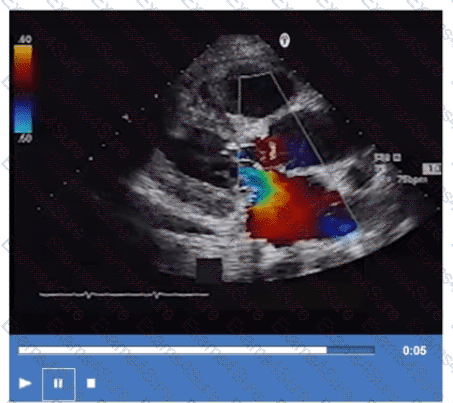

Which finding does peak mitral valve regurgitant Doppler velocity reflect?